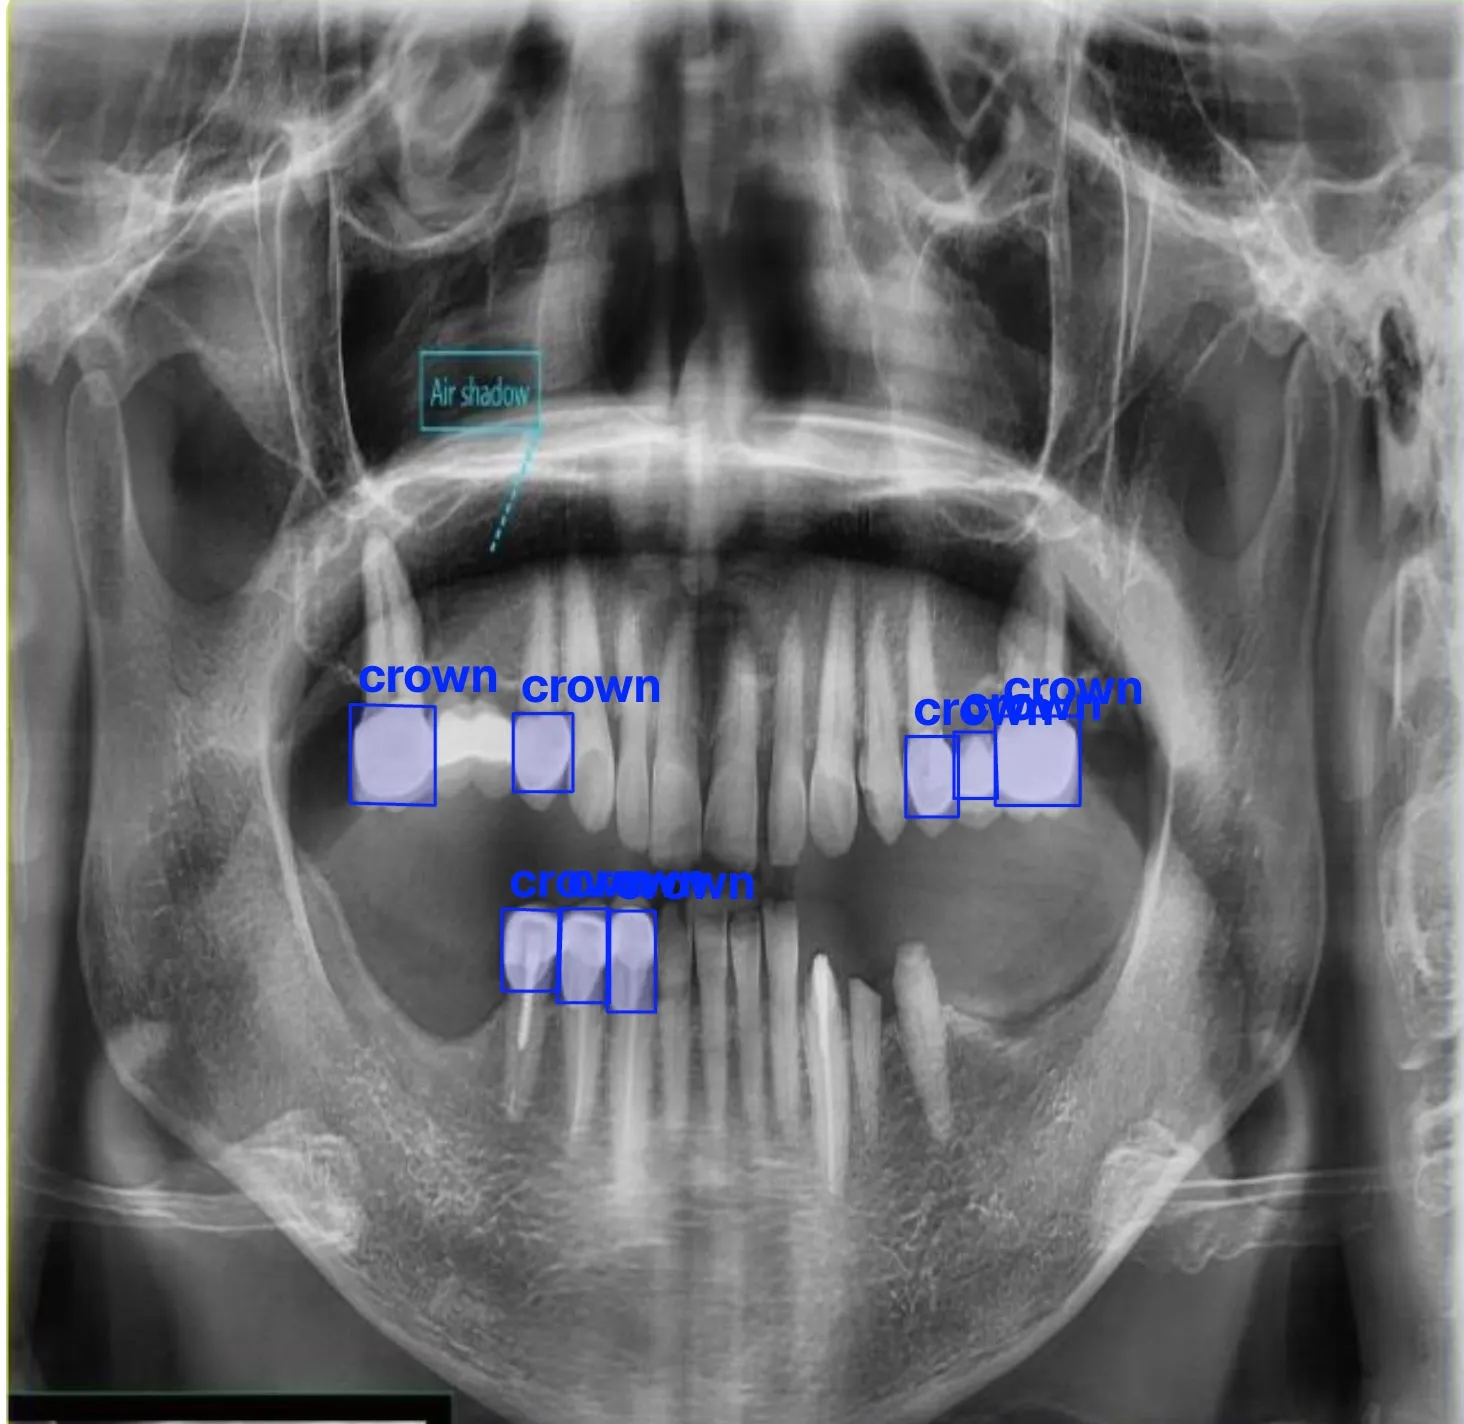

- Crown and bridge work

Fillings, crowns, bridges, and full-mouth rehabilitation for optimal function.